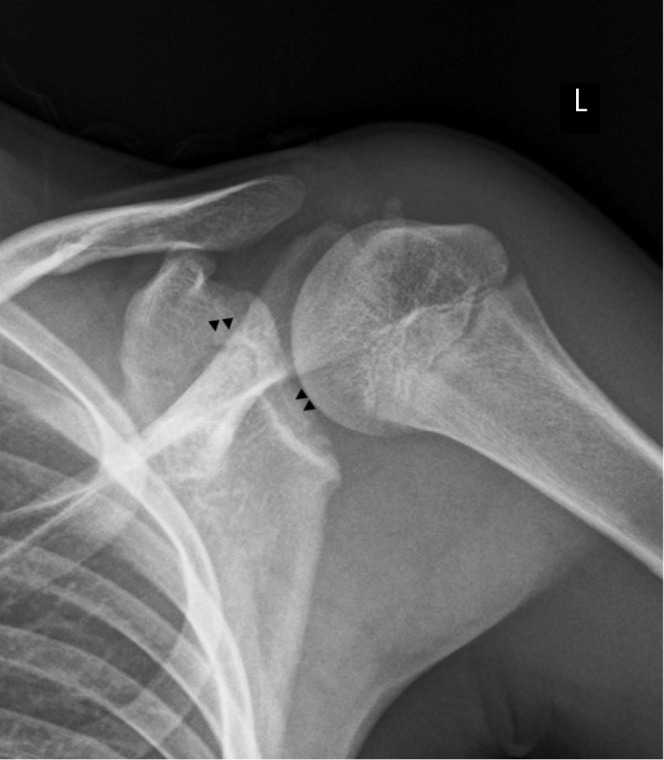

Fig. 1.

Shoulder X-rays of the patient. (A) Anteroposterior radiograph of the right shoulder after trauma in a patient aged 13 years and 6 months. An irregular, radiolucent line is seen extending from the base of the coracoid to the articular surface of the glenoid and another trace appears to be directed posteriorly (▲▲). (B) Scapular Y-projection showing the same discontinuity in the anterior and posterior cortex (*) at the level of the middle third of the glenoid. First interpreted as fracture lines on presentation to the first health center, these images actually correspond to the subcoracoid ossification center and the glenoid growth plates.